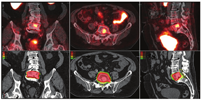

第二,CTVs可以被扩展到包括目前一线影像学未见的疾病区域,并且通常不是一致的CTVs靶点(图3)。第三,转移性疾病的证据表明,单靠局部治疗是无法治愈的。在寡转移性疾病(较低的转移性疾病负荷,在3~5处部位出现不同表达)的背景下,许多医师提供转移导向治疗,旨在局部消融转移灶(图4,图5,图6),转移导向治疗是当前众多临床试验的主题[54]。最后,在某些PET/CT意外显示的弥漫性转移病灶的病例中,放疗可能是无效的。

许多被PET/CT提高了分期级别的患者,转移性疾病的负担有限。对于初始分期有N1影像学证据的患者,目前的治疗方针包括前列腺和盆腔淋巴结放疗及长期雄激素去势治疗[79]。对有N1影像学证据的患者,局部治疗失败后的治疗方法尚不清楚。前列腺癌M1期的患者主要采用雄激素去势治疗。然而,对许多临床医师来说,以不同于全身广泛转移患者的治疗方式来治疗有限的转移病灶(寡转移)患者似乎是合理的(研究者对寡转移前列腺癌有不同的定义,一般指最多有3~5处明显的远处转移)。转移导向治疗,是通过SBRT或转移瘤切除术,伴或不伴有全身系统性治疗的一种正在策划进行中的前瞻性试验策略[80]。前列腺癌寡转移患者是否最终会受益于与全身广泛转移转灶不同的治疗策略目前尚不清楚。不过在任何情况下,随着临床医师采用PET/CT进行初始和复发分期,对这些患者的识别可能会大大增加。

Ghent大学附属医院的寡转移前列腺癌采用积极监测对比转移灶导向治疗(surveillance or metastasis-directed therapy for oligometastatic prostate cancer recurrence, STOMP)研究中(NCT01558427),在寡复发转移的情况下,随机分组的患者使用11C-胆碱PET重新分级进行转移导向治疗,并与观察组进行对比。主要终点是开始雄激素去势治疗的时间。转移导向治疗可将雄激素去势治疗的无瘤生存期从13个月提高到21个月(风险比,0.60;P=0.11)[81]。